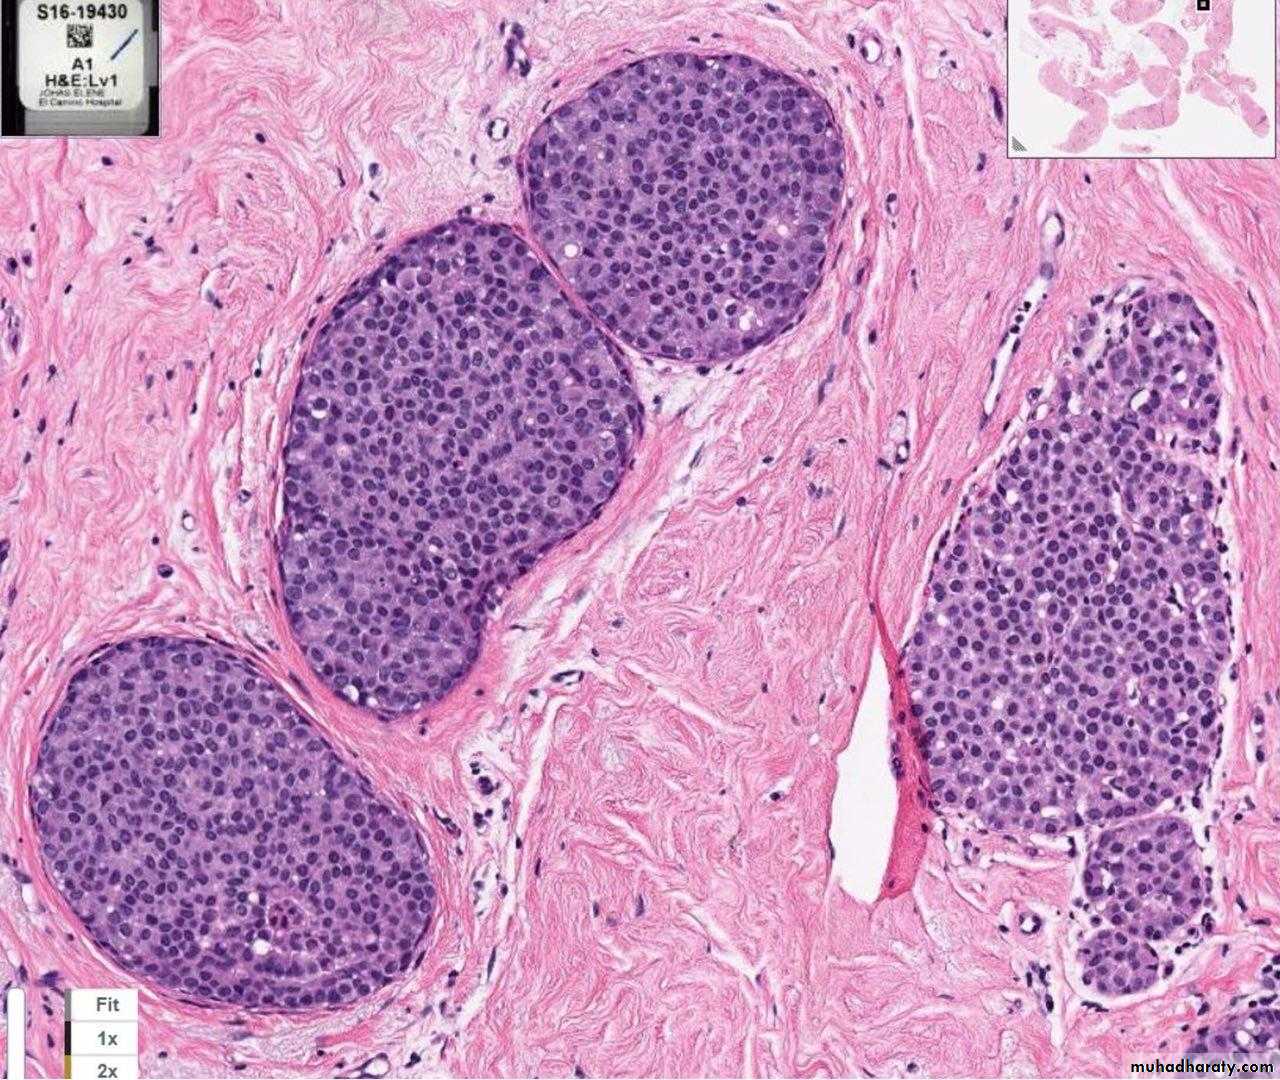

LCIS: TDLU filled and distended by proliferation of small uniform cells which are loosely cohesive, vacuolated cytoplasm.